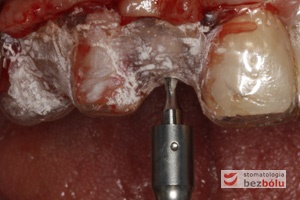

Zagęszczanie kości techniką osteotomową - korzyści płynące z użycia osteotomu to bezpieczeństwo i poprawa gęstości kości

Zagęszczanie kości techniką osteotomową – korzyści płynące z użycia osteotomu to bezpieczeństwo i poprawa gęstości kości